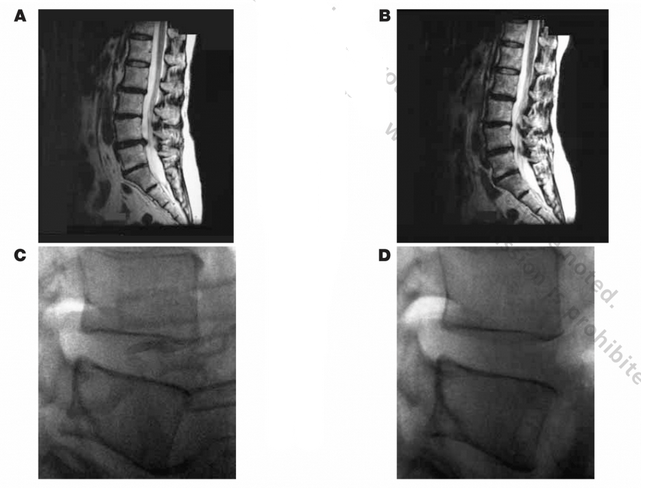

The evolution of technology has led to changes in force application, patient positioning, and the addition of passive restraint systems in the newer nonsurgical spinal decompression devices such as the DRX9000™. Investigators have reported early success with the DRX9000™ system based on objective radiologic observations of intervertebral disk height or measured bulging. In a small series of case studies, a group of investigators added new data to the hypothesis that such decompressive systems can, over time, increase disk volume and reduce herniation, as shown in the MRI findings of a patient (Figures 2A and 2B) and lateral radiograph of an asymptomatic healthy volunteer (Figures 2C and 2D).